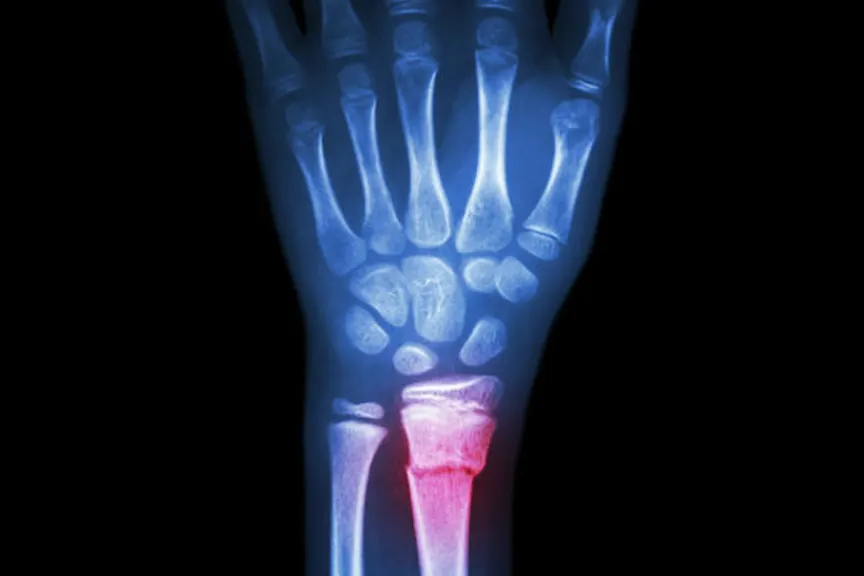

防止骨折的8种方法